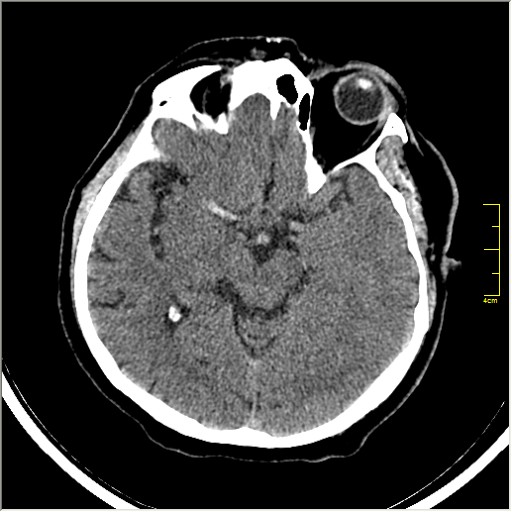

Пациентка Д. 64 года. Поступила с диагнозом ОНМК ???, жалобы на онемение и слабость в левой половине тела.

Ответ: Обратите внимание на правую среднемозговую артерию (MCA); М1 сегмент гиперденсен; сравните с другой стороной.

Этот признак называется [Dense MCA sign]; за счёт наличия тромбоза в её просвете. Этот признак является одним из ранних указующих КТ признаков при ишемическом инфаркте головного мозга. Более подробно об этом вы можете прочитать здесь: http://www.radiologyassistant.nl/en/483910a4b6f14.